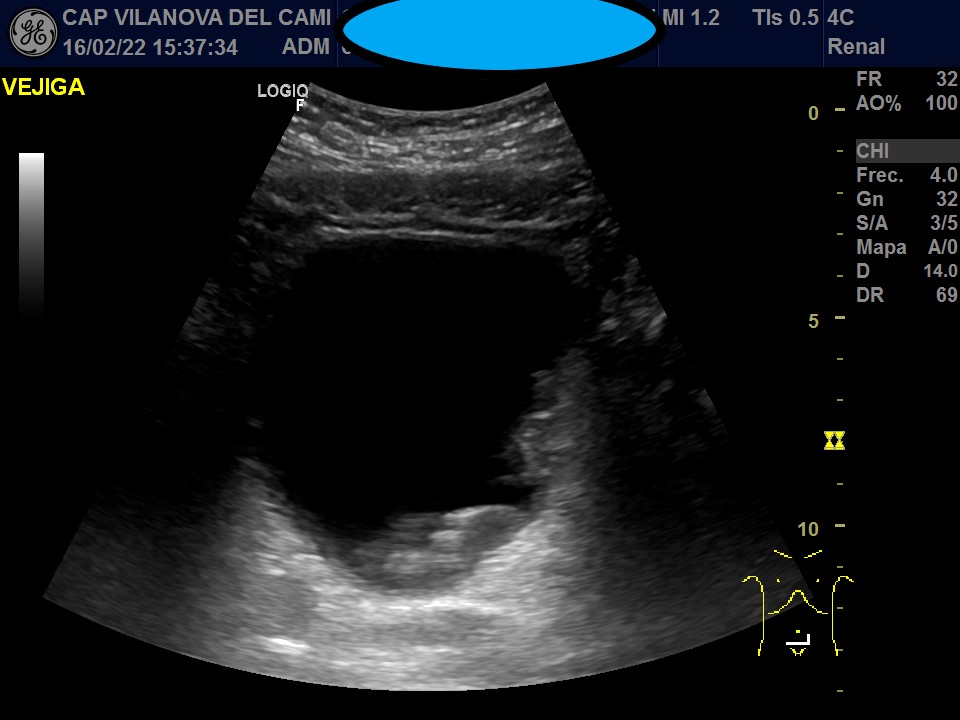

Vejiga urinaria bien distendida, de paredes engrosadas, con imágenes sugestivas de patología intraluminal y parietal. Neoformación irregular en pared posterolateral izquierda y suelo pélvico, que respeta el trígono vesical y la salida del meato ureteral, con captación Doppler color y algunas imágenes hiperecogénicas sugestivas de calcificación en su interior.